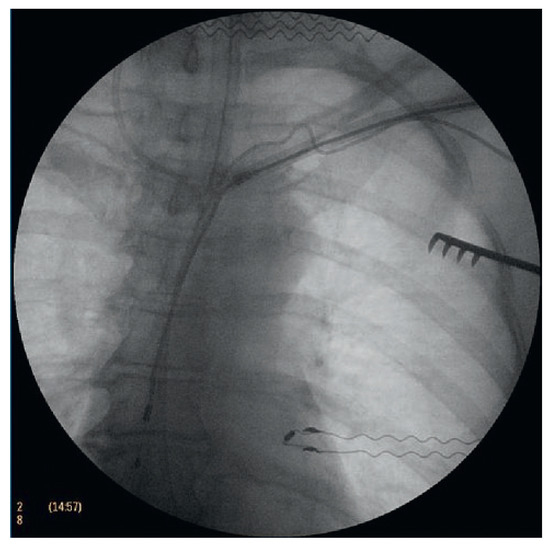

Der 70-jährige Patient wurde uns zugewiesen zur stationären kardialen Rehabilitation bei St. n. mechanischem Aortenklappenersatz wegen schwerer degenerativer Aortenstenose.[...]